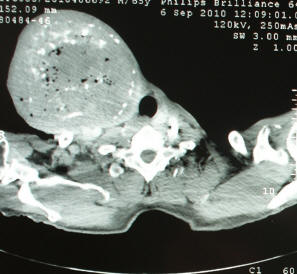

A Case Of Right Paratracheal Ectopic Thyroid, Mimicking

Title: A Case of Right Paratracheal Ectopic Thyroid, Mimicking Metastasis on CT and 18F-FDG PET CT Author: Su Young Kim Subject: Mediastinal ectopic thyroid is quite rare, occurring in less than 1% of all ectopic thyroids. ... Retrieve Full Source